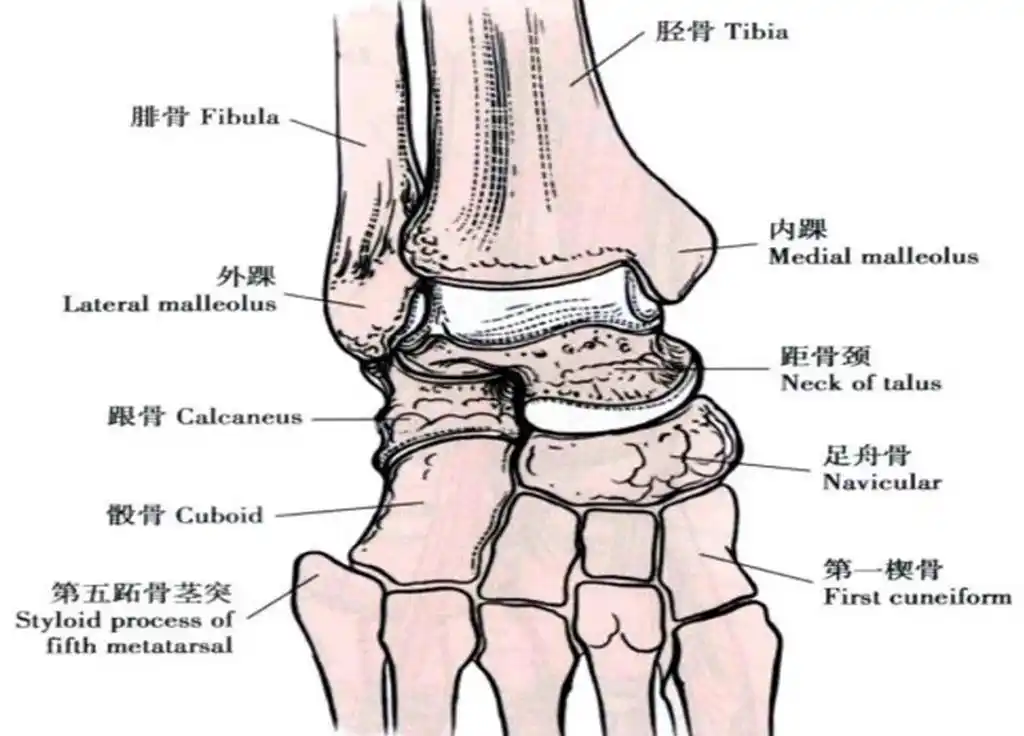

x线解剖 | 踝关节解剖

完美33张踝关节解剖高清图解

踝关节mri解剖和常见损伤类型

解剖踝关节系统解剖图冠矢轴mri

踝关节mri解剖及7种常见损伤类型